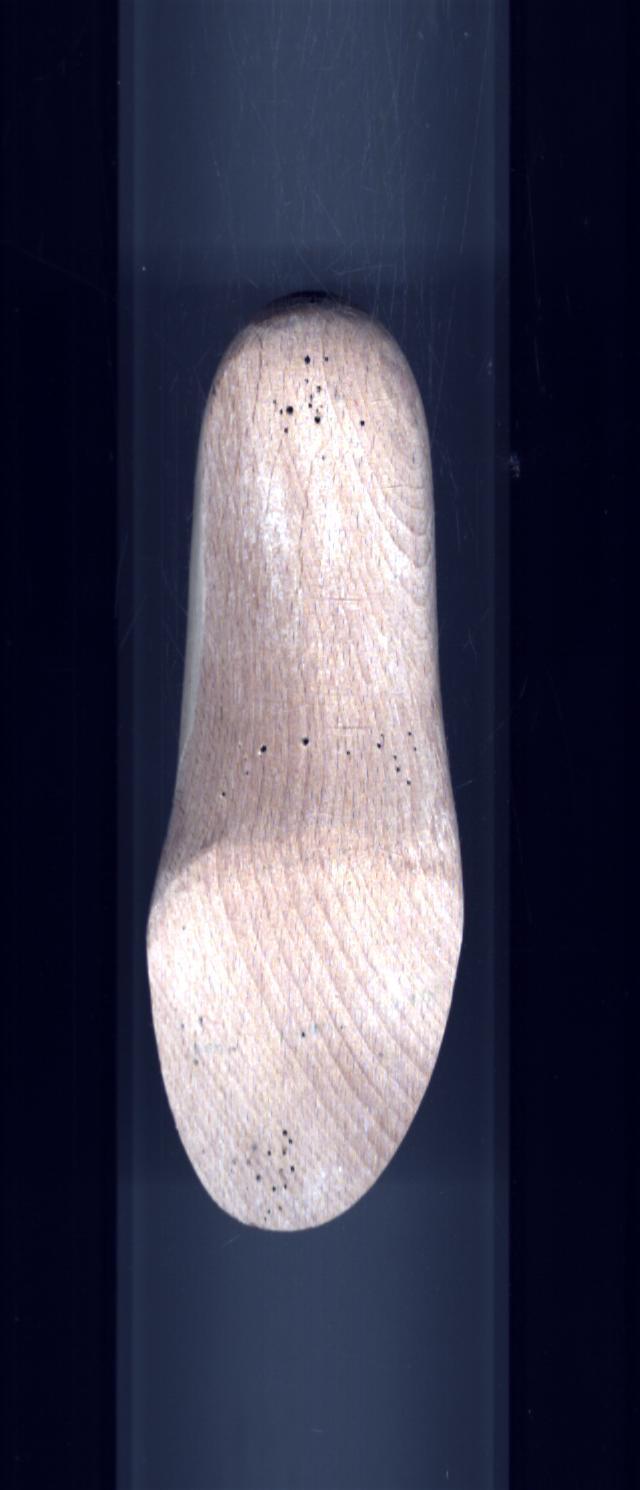

- Bout de la Forme

- Forme

MontanteForme de serie semi-mesure

- Podologique

Gauche Droite Talon de la Forme 15 15 Talon de la Chaussure 15 15 Type orthèse Confort Confort Sous Talon 10 10 Molysère TETES META TETES META Ligne Des Flancs 10 10 Relevé 15 15 Semelle d'Amplitude 5 5